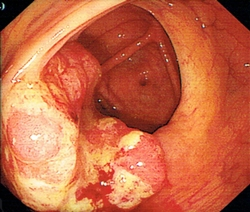

大腸癌是本港第3常見的癌症,亦是本港致命癌症中的第2位。大腸癌篩查可及早識別未出現病徵的大腸癌患者或高危人士,讓其及早接受治療,大大提高治癒率,而在大腸鏡檢查過程中切除大腸腺瘤,則可避免腺瘤演變成癌症。經計劃確診大腸癌的個案中,約2400宗已進行初步分析,結果顯示約56%屬於早期個案,治癒率較高。